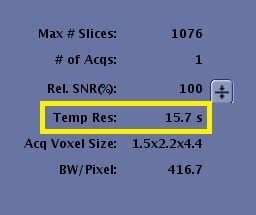

- From the Workflow Manager, select the DISCO series and click Setup. From the Scan Parameter and Details screens make adjustments, as needed.The effective temporal resolution of the wash-in phases (time interval from one wash-in phase to the next phase) value is displayed on the Scan Parameter screen. Note the value may change as you alter other scan parameters.

Figure 2. Scan parameter screen advisory area